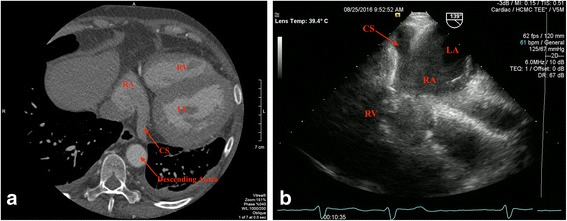

With the newly detected thrombus and history of paroxysmal atrial fibrillation, our patient was started on warfarin for therapeutic systemic anticoagulation. At her 3-month out-patient visit, her liver enzymes had normalized, and TEE and gated cardiac CT, optimal imaging modality for assessment of the entire cardiac venous system, showed complete resolution of the CS thrombus (Fig. 2a and b). In light of paroxysmal atrial fibrillation and development of spontaneous CST, the decision was made at 6-month follow up to continue anticoagulation long term. Her subsequent clinical course was remarkable for development of polymicrobial intra-abdominal abscess (Enterococcus faecalis, Escherichia coli, and Candida albicans) 8 months after the index event requiring drain placement and 4 weeks of antibiotic therapy. She was ultimately discharged to sub-acute rehabilitation with plan for a partial colectomy to be done in the coming months after improvement in her functional capacity.

Fig. 2.

a Gated cardiac computed tomography at the coronary sinus level showing patent coronary sinus with resolution of the prior filling defect after 3 months of systemic anticoagulation. b Transesophageal echocardiogram at the gastroesophageal junction positioned at 139° confirmed patent coronary sinus. CS coronary sinus, LA left atrium, LV left ventricle, RA right atrium, RV right ventricle